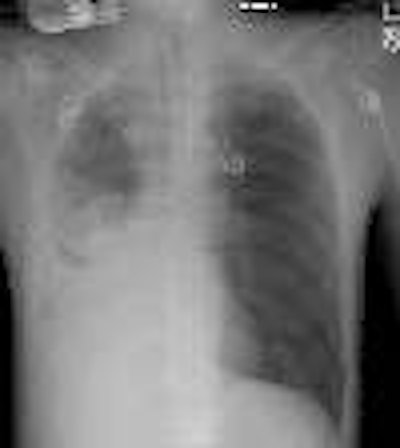

Torsio3aThe post-operative chest radiograph demonstrated complete shift of the cardiac silhouette into the right hemithorax, however, the cardiac apex appeared to be on the right- a finding which was suspicious for cardiac torsion.